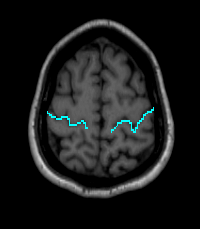

Trace the Central Sulcus in the axial view. Drawing on several slices in the axial view is beneficial (Fig 6).

Figure 6